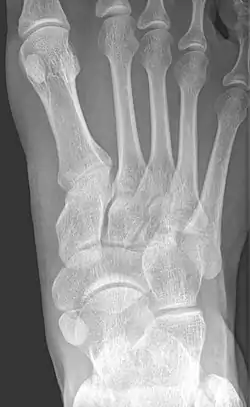

![]() X-ray of the foot showing an accessory navicular bone | |

An accessory navicular bone is an accessory bone of the foot that occasionally develops abnormally in front of the ankle towards the inside of the foot. This bone may be present in approximately 2-21% of the general population and is usually asymptomatic.[1][2][3] When it is symptomatic, surgery may be necessary.

From left to right: Type 1, 2 and 3